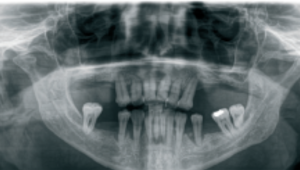

a. Situación clínica inicial del paciente con compromiso periodontal avanzado y movilidad severa de las piezas dentales. Evaluación radiológica previa al tratamiento para el análisis del volumen óseo y la planificación de implantes.